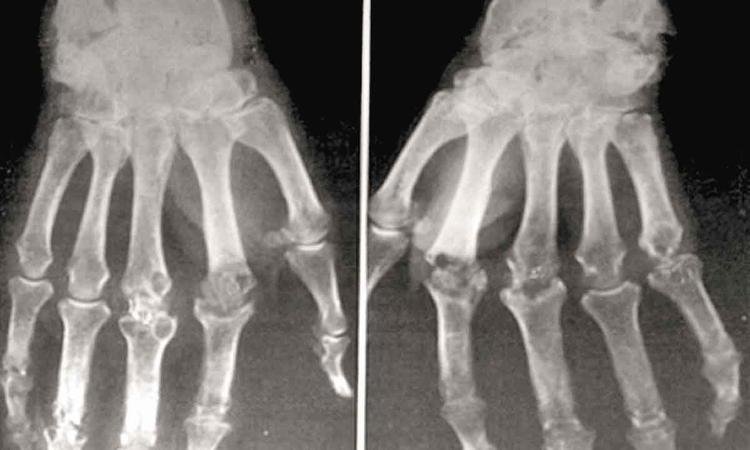

Artrite psoriásica: Como tratar?

Estimativas indicam que cerca de 50 milhões de pessoas têm diagnóstico de artrite psoriásica por todo o mundo. A doença se manifesta em diversos órgãos do corpo, articulações e pele, causando dor, fadiga, rigidez nas articulações e descamações. Segundo Marcelo Pinheiro, membro da Comissão de Espondiloartrites da Sociedade Brasileira de Reumatologia, a artrite psoriásica causa prejuízos na qualidade de vida dos pacientes. Com isso, é importante o diagnóstico precoce e o tratamento correto, que pode variar de acordo com o sistema imunológico.